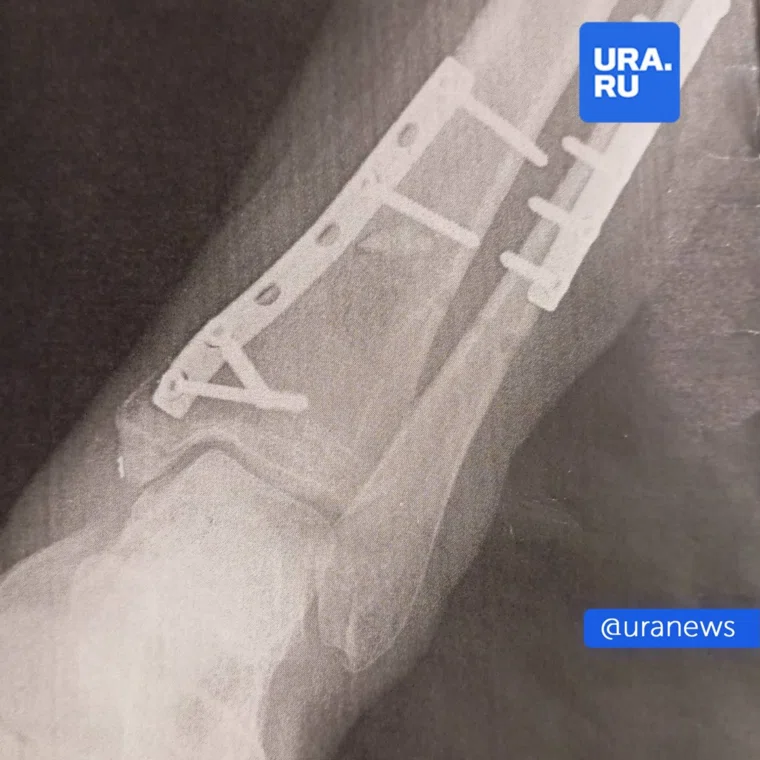

В результате у женщины были раздроблены кости, ей потребовалось три операции и установка спиц для восстановления. По словам пострадавшей, она два месяца не могла ходить, а руководство клуба не связалось с ней после инцидента. Евгения, занимавшаяся спортом с 18 лет и посещавшая этот фитнес-клуб более 500 раз за 6 лет, также отметила, что инструктаж по технике безопасности в зале не проводился.

Кости ноги раздробило